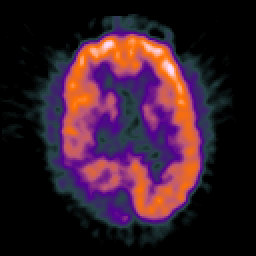

Glioma Overlay -- Slice #13

[Home][Help][Clinical] Slice 13